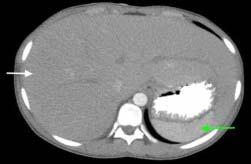

Hospital records such as admission certificate, treatment records, bed head tickets were reviewed for the purpose of selection of cases and controls (Fig 1).

During the reference period those attending the post COVID-19 follow-up clinic were included into the study

Those who provided written, informed consent, and satisfied the inclusion and exclusion criteria were included in the study. (n=64)

Medical records of the subjects were reviewed and participants were consecutively enrolled and categorised as cases and controls*

Three controls were taken against each case, matched appropriately with respect to age (±2 years) and sex.

Those who had severe COVID-19 disease (as per WHO guidelines) were taken as cases (n= 16)

Those who did not have severe COVID-19 disease (ie, mild/moderate disease per WHO guidelines) were taken as controls. (n=48)

Participants were interviewed using a pre-tested, pre-designed schedule.

*Medical records included admission certificate, discharge certificate, treatment records, bed head tickets.

Fig 1 — Chart showing the selection of cases and controls